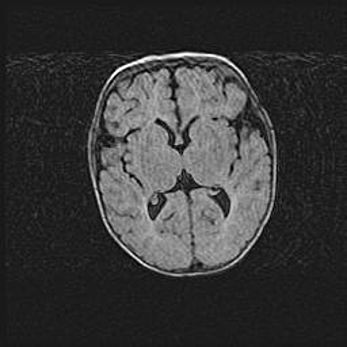

Церебральная ишемия II.

Возраст: 5 дней

Вес: 3400 г

Пол: женский

Окружность головы: 35 см

Срок гестации: 39 недель

Церебральная ишемия – это заболевание, характеризующееся недостаточностью (гипоксией) либо полным прекращением (аноксией) снабжения мозга кислородом по причине закупорки одного или нескольких сосудов. Это приводит к  что метаболическим расстройствам различной степени тяжести в тканях головного мозга, развитию коагуляционных некрозов и гибели нейронов.